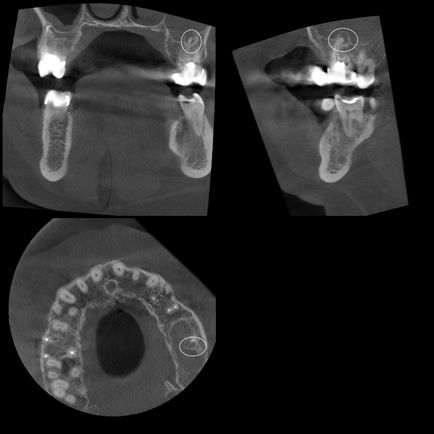

A perforáció a foggyökér és a ciszták keletkezését mezhkornevyh

Terápia: jelenléte rejtett üregek